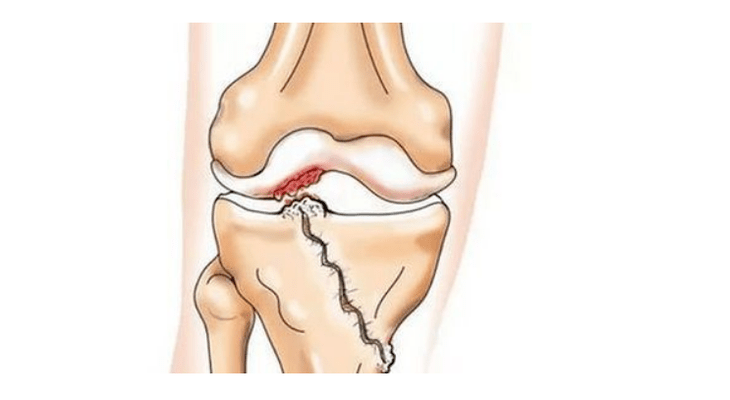

- injuries (fracture, rupture of the meniscus and anterior cruciate ligament).Unfortunately, in any person, regardless of age, this injury leads to excessive pressure on the cartilage.Fracture of any part of the bone covered with cartilage is accompanied by the formation of an unevenness - "step".In this area, when moving, abrasion occurs and arthrosis forms;

With arthrosis (osteoarthrosis), in addition to the progressive destruction of cartilage, loss of elasticity and shock-absorbing properties, bone is gradually involved in the process.Under load, sharp edges (exostoses) appear, which are mistakenly considered "salt deposits" - with classic arthrosis, no salt deposits occur.As arthrosis develops, it continues to "eat" the cartilage.Then the bones become deformed, cysts form there, all joint structures are affected, and the legs become bent.